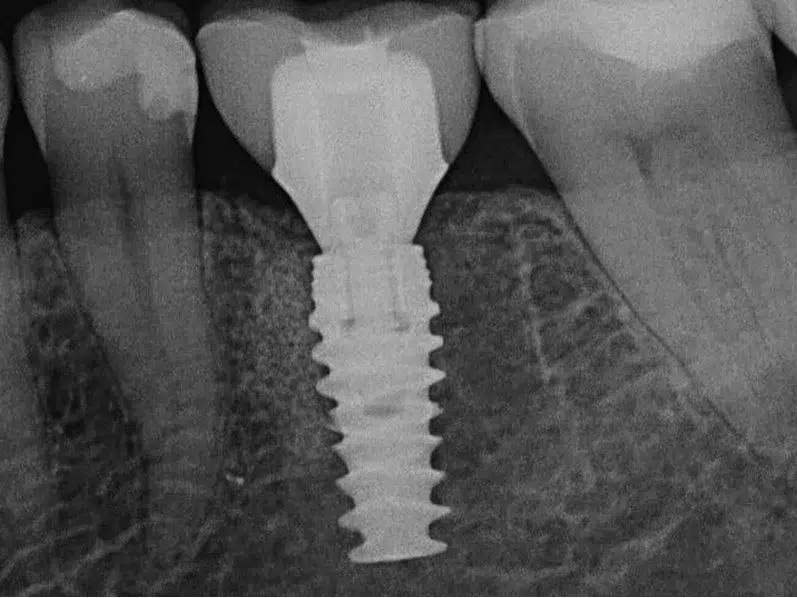

Implanttihoidossa leukaluuhun asetetaan titaaninen, ruuvin muotoinen keinojuuri, jonka päälle kiinnitetään hampaan näkyvä osa, kruunu. Hyvin hoidettuna implantti kestää vuosikymmeniä, usein jopa kantajansa loppuelämän ajan.

Immediaatti-implantointi lyhentää implanttihoidon kestoa, vähentää kirurgisten toimenpiteiden määrää ja parantaa estetiikkaa. Välittömässä implanttihoidossa keinojuuri ja väliaikainen hammaskruunu asetetaan hampaan poistokuoppaan heti hampaan poiston jälkeen, yhden vastaanottokäynnin aikana.

Ennen immediaatti-implanttihoidon aloittamista erikoishammaslääkäri tekee suun kliinisen tutkimuksen, jota täydennetään röntgenkuvilla. Perusteellinen tutkimus luo suuntaviivat hoidon toteuttamiselle. Hoito voidaan tehdä terveeseen ja tulehduksettomaan suuhun.